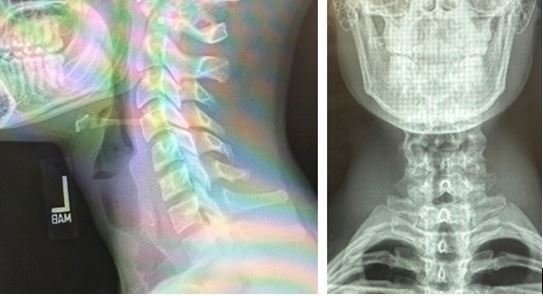

Initial diagnostic testing: